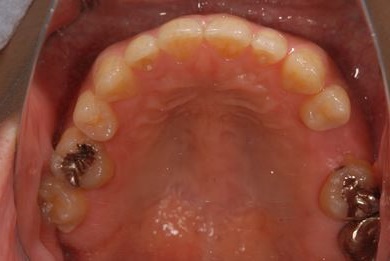

インプラントの症例写真 IMPLANT

骨再生インプラント治療

| 性別/年齢 | 男性 / 34歳 | ||||||||||||||||||||||||||||||||

| 治療方針 | ソケットリフトにて上顎洞を拳上し、インプラント治療を可能にする。 | ||||||||||||||||||||||||||||||||

| 治療内容 | インプラント1本(ソケットリフト)、メタルボンドセラミッククラウン1本 | ||||||||||||||||||||||||||||||||

| 総治療費 | 547,838円 | ||||||||||||||||||||||||||||||||

| 治療期間 | 4ヶ月 |